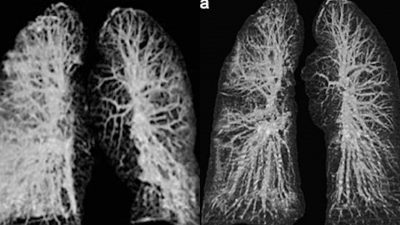

Los especialistas del Instituto Nacional de Enfermedades Infecciosas en Roma estudiaron los cuerpos de los pacientes de 65 y 67 años y detectaron, mediante rayos-X y tomografías computarizadas, un gran deterioro en la función de los pulmones.

Cuando coronavirus ataca los pulmones, provoca una inflamación en las membranas mucosas, lo genera un daño en los alvéolos pulmonares, que tienen que trabajar más para suministrar oxígeno a la sangre que circula por todo el cuerpo y eliminar el dióxido de carbono para que se pueda exhalar. La inflamación y el daño al flujo de oxígeno pueden causar que dichas áreas en los pulmones se llenen de fluido, pus y células muertas.